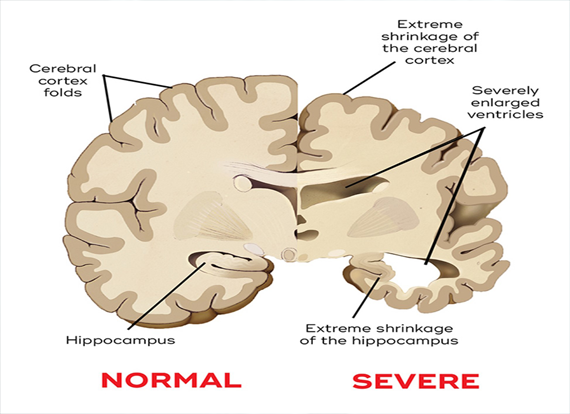

– Dementia